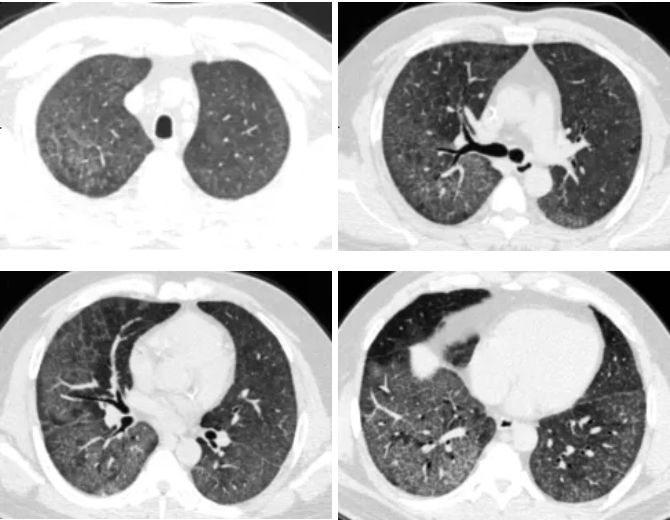

QQ截图20260326083350

▲ 灌洗后胸部CT

术后患者生命体征稳定,已完全脱离氧气,日常生活无明显闷喘。